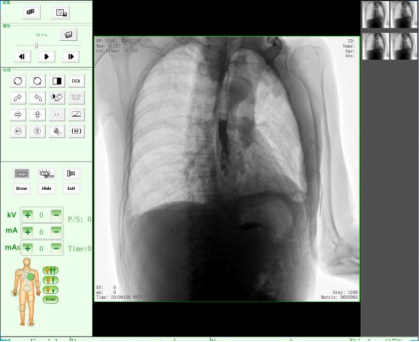

隨著人們健康意識不斷提高,越來越多人重視健康體檢,而數(shù)字化DR拍片幾乎是體檢必檢項目之一,胸片結(jié)果正常DR報告顯示為:胸廓對稱,兩側(cè)肋骨、肋間隙正常;兩肺紋理清晰,未見明顯實質(zhì)性浸潤;兩側(cè)肺門和縱隔影來見明顯異常;心臟大小、形態(tài)在正常范圍內(nèi);膈肌平滑,雙側(cè)肋膈角銳利時,則說明您一切正常。那么,數(shù)字化DR胸片報告不正常的結(jié)果有哪些呢?

3、兩肺紋理增粗、紊亂,呈網(wǎng)狀或條索狀、斑點狀陰影。

老慢支,肺氣腫,肺心病,這時您的數(shù)字化DR片可能會呈現(xiàn)這種胸片,當(dāng)進(jìn)一步發(fā)展時,將會出現(xiàn)兩肺透亮度增加。由于肺泡過度通氣致使X光胸片上黑化度增加,即越黑透亮度越大。哮喘發(fā)作時同樣可見兩肺透亮度增加,呈過度充氣狀態(tài)。當(dāng)然,X線攝影條件過高或是顯影時間過長也會導(dǎo)致這樣。

如果臨床表現(xiàn)為在原有咳嗽、咳痰的基礎(chǔ)上有逐漸加重的呼吸困難,甚至有胸悶、氣急、桶狀胸。常見的嚴(yán)重肺氣腫、肺大泡還會導(dǎo)致氣胸,也就是胸腔內(nèi)的氣體將肺壓縮,使被壓縮的肺與胸壁間出現(xiàn)透明的含氣區(qū),其中不見肺紋理。這些多是由白變黑的異常。